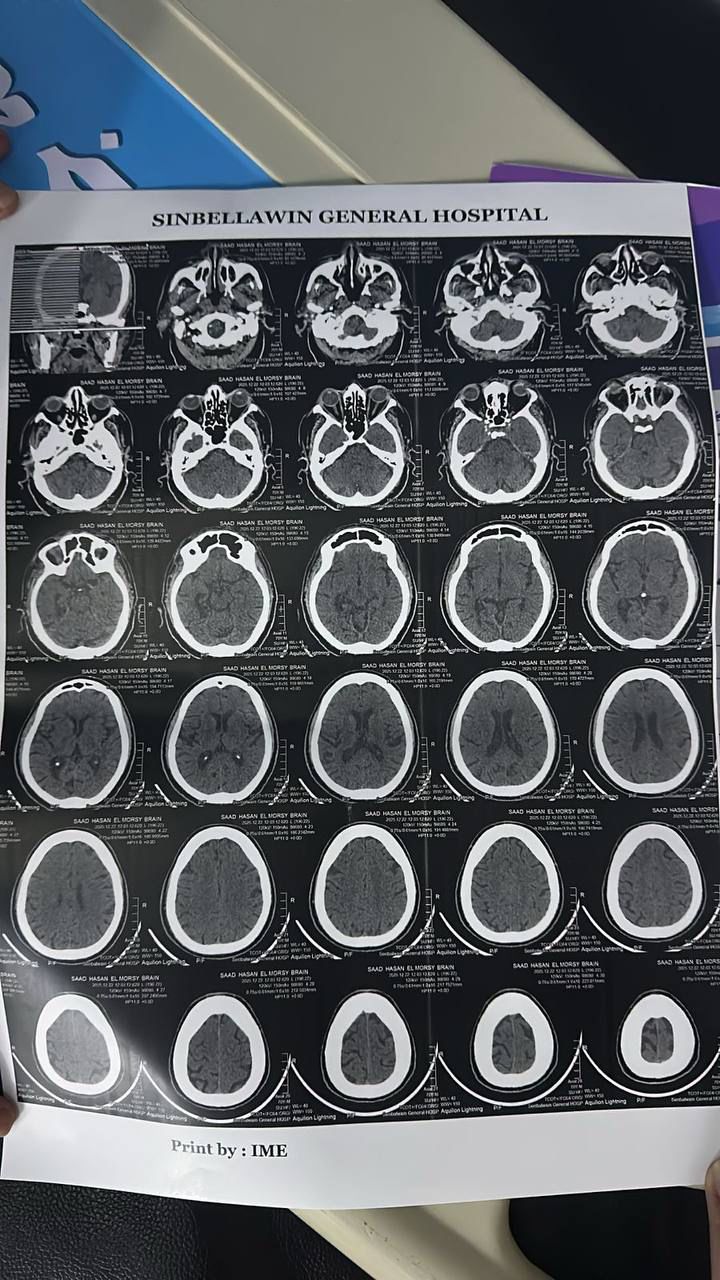

نجحت وحدة إذابة الجلطات بمستشفى السنبلاوين العام بالدقهلية، في إنقاذ حالتين حرِجتين، الأولى لمريضة تبلغ من العمر 65 عامًا وتعاني من ارتفاع ضغط الدم، كانت قد حضرت إلى قسم الاستقبال وهي تعاني من ضعف في الجانب الأيمن من الجسم والوجه.

وبعد إجراء الفحوصات والأشعة اللازمة، تم حجزها وإعطاؤها حقن إذابة الجلطات، وأسفر ذلك عن تحسن ملحوظ في درجة الوعي وخروجها بعد استقرار حالتها.

وأوضح المستشفى في بيان له، أن الحالة الثانية كانت لمريض يبلغ من العمر 70 عامًا ويعاني من مرض السكري، حضر وهو يعاني من ضعف في الجانب الأيمن وثقل في الكلام.

وبعد إجراء الفحوصات اللازمة وإعطائه حقن إذابة الجلطات، ظهر تحسن سريع في الطرفين العلويين، وخرج المريض بحالة مستقرة.